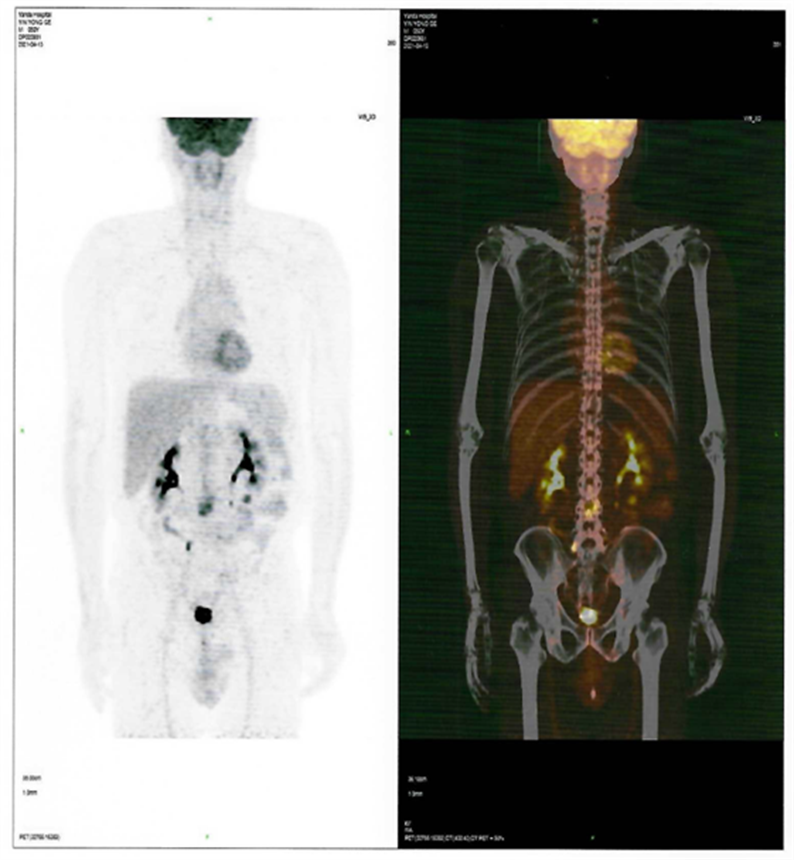

患者CAR-T 前后PET-CT檢查結(jié)果對比圖

CAR-T治療前

CAR-T治療后30天

回輸后一度出現(xiàn)了一級CRS反應(yīng),癥狀可控,5月26日,回輸后+28天復(fù)查PET-CT顯示CR(完全緩解)。預(yù)祝黃山先生接下來的治療一切順利!